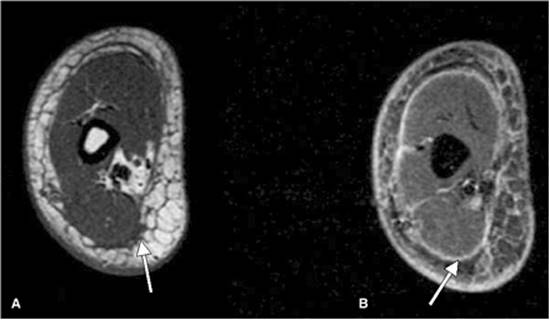

Imaging studies, in particular computerized tomography, have shown with great sensitivity the presence and extent of gas or subcutaneous air. MRI T2-weighted images (Fig. 107.12) can show well-defined areas of high signal intensity significant for tissue necrosis, and absence of gadolinium contrast enhancement on T1 images reliably detects fascial necrosis in those who might require operative debridement. Ultrasound, although able to detect fluid or gas within soft tissues, requires the probe to be applied directly on the involved tissues. Many patients with NF, especially those with Fournier's, may not tolerate this, plus there may be a limitation of the anatomic site causing difficulty in visualizing deep tissues. Yen et al. (22) found ultrasound to have a sensitivity of 88% and a specificity of 93% (positive predictive value of 83%). Their diagnostic criteria included diffuse thickening of the subcutaneous tissue accompanied by fluid accumulation more than 4 mm in depth along the fascial layer.

Magnetic resonance imaging (Fig. 107.12)

T2-weighted images. T1-weighted images

Unstable patients unable to tolerate time required for study

High sensitivity for extent of involvement

000964

Figure 107.12. T1-weighted and T2-weighted magnetic resonance (MR) image of the lower extremity showing fascial thickening and fluid accumulation between the subcutaneous tissues (A) and fascial layer (B), respectively, in this patient with necrotizing fasciitis.